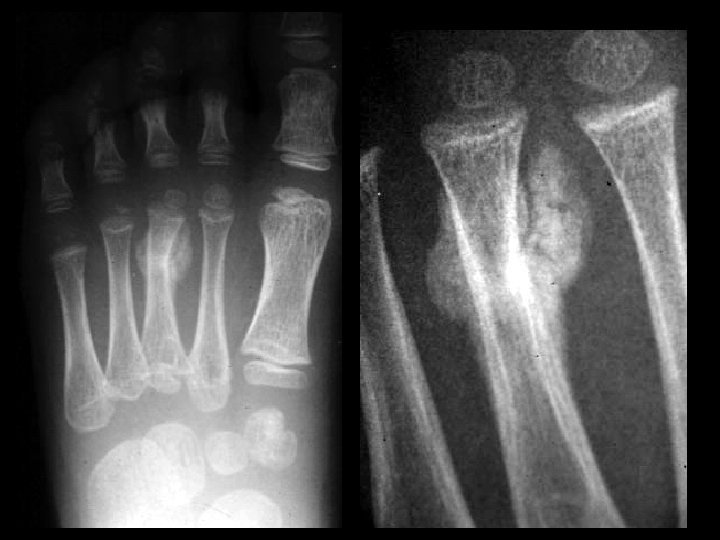

Stress fracture • Findings: – Slightly angulated fracture of the distal 3 rd metatarsal – Periosteal reaction – Surrounding calcified osteoid matrix = callus • ddx: – Osteosarcoma with pathologic fracture